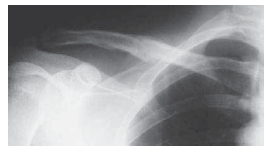

Meticulous preoperative planning is the cornerstone of successful intramedullary clavicle fixation. The diagnostic workup begins with a comprehensive physical examination. On visual inspection, the surgeon will frequently observe notable swelling, ecchymosis, and a gross deformity characterized by the affected shoulder drooping downward, forward, and medialward. The skin must be meticulously inspected for tenting, abrasions, or the classic transverse ecchymosis indicative of a seatbelt shoulder strap injury. Gentle palpation will reveal point tenderness and crepitus. Crucially, the degree of clinical shortening must be quantified by measuring the linear distance from the sternal notch to the acromioclavicular joint bilaterally and calculating the deficit. A rigorous neurovascular examination is mandatory to rule out brachial plexus traction injuries or subclavian vessel compromise.

Radiographic evaluation requires a minimum of two high-quality orthogonal projections. A standard anteroposterior (AP) view is often obscured by the overlapping ribs and thoracic anatomy. Therefore, a 45-degree cephalic tilt view and a 45-degree caudad tilt view are absolutely essential to accurately delineate the fracture pattern, assess the degree of comminution, and evaluate the superior-inferior displacement. In clinical practice, a modified 20- to 60-degree cephalic tilt view is frequently employed to throw the clavicle free of the thoracic cage, providing an unobstructed silhouette of the osseous architecture. A broad-cassette AP view encompassing bilateral clavicles is highly recommended to precisely calculate radiographic shortening. While advanced imaging is rarely mandated for standard midshaft fractures, a computed tomography (CT) scan with three-dimensional reconstructions can be invaluable for evaluating complex multiplanar deformities, suspected intra-articular extension, or delayed unions.

Clinical & Radiographic Imaging Archive